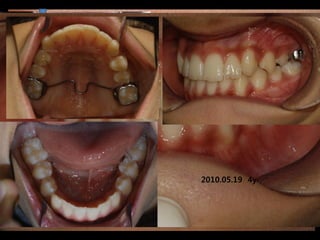

2009.03.06 2y 4y

2010.05.19 9m

C.C

• Lower ant. crowding

Dx

• Deepbite, rhinitis, mentalis action

Goal

• Establish nose breathing and normal swallowing

pattern with T4K